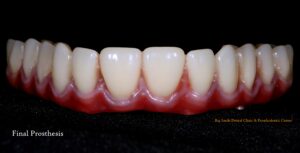

Upon his return six months later, we examined the implants and temporary denture, finding everything in excellent condition. We then proceeded with the fabrication of the final permanent hybrid denture prosthesis, which was completed within ten days. The result was highly satisfying and aesthetically pleasing. The patient left our Big Smile Dental Clinic & Prosthodontic Center extremely happy with the treatment and services he received.

Fig: Post-operative photograph after Permanent hybrid denture placement